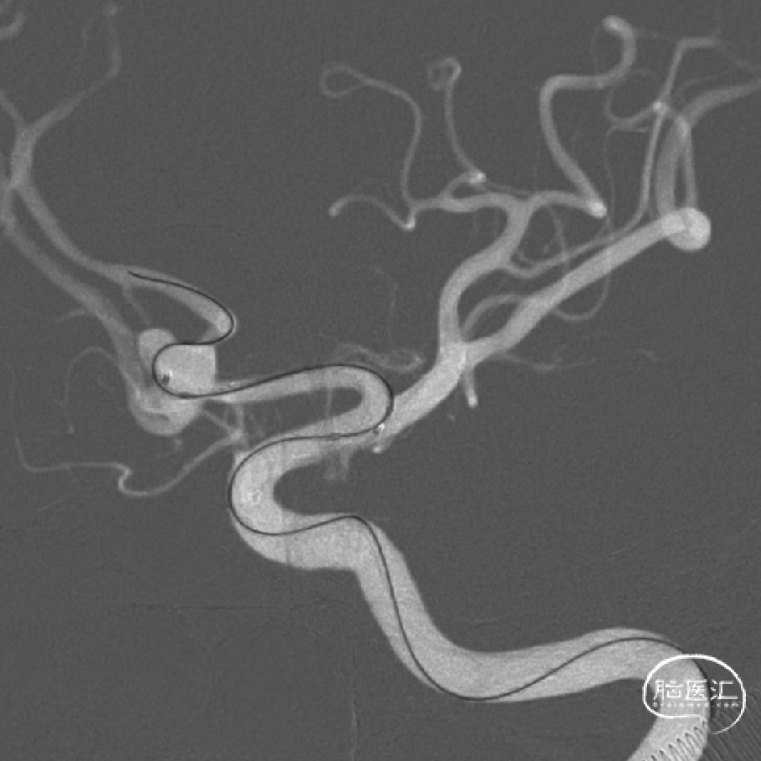

3、双微导管填圈后,准备送入Atlas 3*15mm。

7、释放Atlas支架。

术后影像

释放支架后继续填塞至动脉瘤不显影。双侧A1-A2显影良好。患者术后神经体检正常。